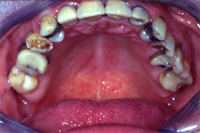

Ein 64 Jahre alter Patient wünscht eine Zahnsanierung (Abb. 1 und 2). Nach intensiver Abklärung des Zustandes der einzelnen Zähne der Restbezahnung sowie der Gesamtsituation (Abb. 3) und der Kostenzusammenstellung wurde folgende Therapie durchgeführt:

Ästhetisch wie auch funktionell entstand ein ausserordentlich schönes Resultat (Abb. 5 und 6).